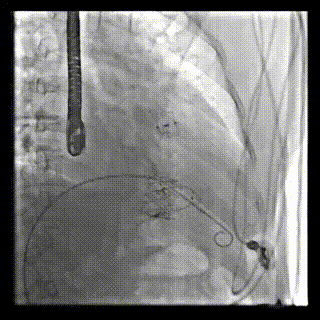

2021年12月24日,復(fù)旦大學(xué)附屬中山醫(yī)院葛均波院士團(tuán)隊(duì)成功應(yīng)用LuX-Valve Plus為一例極重度三尖瓣反流(TR)合并房顫、房缺的患者完成了經(jīng)血管三尖瓣置換術(shù),這是在前基礎(chǔ)上,本周完成的第三例經(jīng)血管三尖瓣置換手術(shù),葛均波院士、周達(dá)新教授等與心外科魏來教授、賴顥教授,心超室的潘翠珍教授、李偉教授及麻醉科的郭克芳教授共同完成了本周手術(shù),均獲得圓滿成功!患者術(shù)后超聲顯示無TR,臨床癥狀明顯改善。本周手術(shù)的成功也為L(zhǎng)uX-Valve Plus救治性臨床研究添上了濃墨重彩的一筆。

本周三例接受LuX-Valve Plus經(jīng)血管三尖瓣置換術(shù)的患者中,第一例患者為冠狀動(dòng)脈旁路移植術(shù)+Bentall+二尖瓣成形術(shù)后;第二例患者為永久起搏器植入術(shù)后,存在跨三尖瓣導(dǎo)線;第三例患者合并房顫、房缺及左心耳封堵術(shù)后。

三例患者入院后,葛均波院士團(tuán)隊(duì)周達(dá)新教授、潘文志教授、張?jiān)床┦俊㈥惿┦考靶某业呐舜湔浣淌?、李偉教?/strong>對(duì)患者的情況進(jìn)行詳細(xì)評(píng)估和討論,最終決定為三例患者選擇LuX-Valve Plus40mm、50mm和50mm型號(hào)的瓣膜進(jìn)行手術(shù)治療。手術(shù)后即刻拔除氣管插管,術(shù)后患者三尖瓣反流癥狀得到顯著改善,復(fù)查心超結(jié)果顯示人工三尖瓣瓣膜支架固定穩(wěn)定,瓣葉關(guān)閉形態(tài)未見異常,未見明顯反流。